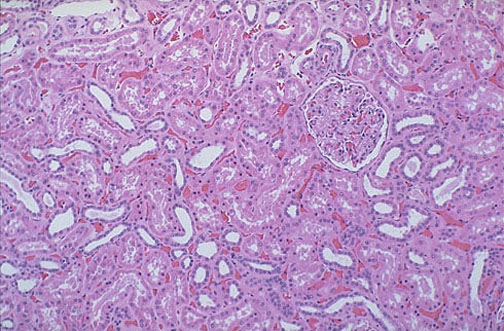

A normal

glomerulus

within the renal cortex seen at medium power has surrounding tubules. The

proximal tubules

have a taller, pinker epithelium compared to the thinner epithelium of the

distal tubules

.